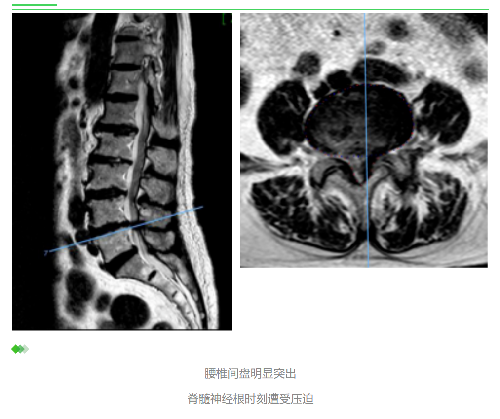

终于来到深圳市中医院就诊。曹主任先帮我做了详细的体格检查,然后让我做CT看看情况。 没想到CT报告提示腰椎间盘脱出(说明腰椎间盘突出的程度明显比以前加重了),而且突出的很大一部分掉到了椎管里。

椎管是脊柱上的一条骨性通道,里面通行着脊髓,而脊髓则是直接连接着大脑的一条神经主干,全身肢体上的所有神经基本都是由脊髓分出来的。椎间盘突出,特别是较大的突出,很容易造成神经的压迫,从而引起症状。

曹主任根据体格检查和CT报告,耐心地帮我分析病情:

从片子上看,腰部的椎间盘突出比较严重,腰部神经受到了影响,出现了明显的症状,严重影响生活,片子表现跟临床表现相符合,因此诊断十分明确。

陈伯原本患有腰椎间盘严重突出,几乎将该节段椎管所有空间都占据了,神经时刻都遭受着严重的损伤,这种情况下,保守治疗方案起到的作用微乎其微,即使能取得疗效也会很快复发,直至神经发生不可逆的损伤,这时再做手术也为时已晚。